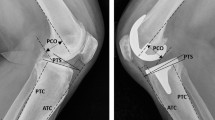

Preoperatively available lateral radiographs were used to measure the medial PTS. To avoid measurement inaccuracies related to malrotated radiographs, the posterior femoral condyle overlap was measured and lateral radiographs with > 6 mm overlap were excluded [15, 16]. The medial PTS was measured using a previously described technique [17, 18]. First, the proximal tibial shaft axis was determined as a line connecting the centers of two circles located 5 cm and 15 cm distal to the joint line, respectively, which touched the anterior and posterior cortex of the tibia. Next, a tangential line was drawn to the medial tibial plateau. Finally, the angle between the proximal tibial shaft axis and the line tangential to the medial tibial plateau was subtracted from 90° to obtain the medial PTS (Fig. 1). Posterior tibial slope measurements were performed by observer one (PWW) using Philips iSite PACS (Koninklijke Philips N.V., Amsterdam, The Netherlands), which allows a measurement accuracy of 0.1 mm and 0.1°, respectively. To ensure intra- and interrater reliability of measurements, intraclass correlation coefficients (ICC) were calculated. For this, ten lateral knee radiographs were randomly selected and the medial PTS was measured three times at 2-week intervals by observer one (PWW) and once each by observer two (NNW) and three (JDH). Excellent intrarater (ICC, 0.99 95% CI [0.98, 0.99]) and good-to-excellent interrater (ICC, 0.92 95% CI [0.76, 0.98]) reliability of measurements was found.

Posterior tibial slope (PTS) measurement. Preoperative strict lateral radiograph of a right knee with isolated posterior cruciate ligament injury and a medial PTS of 6.7°. To obtain the medial PTS, the angle between the proximal tibial shaft axis (line 1) and a tangential line to the medial tibial plateau (line 2) was subtracted from 90°